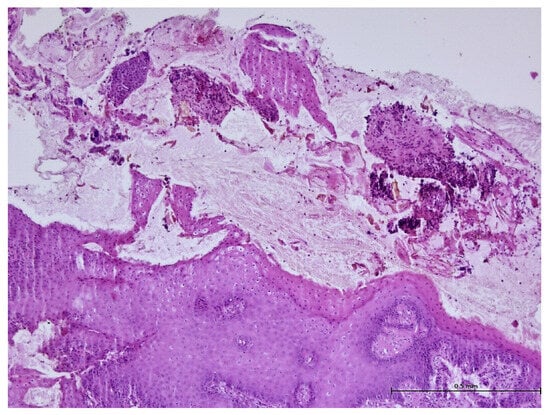

3. Results